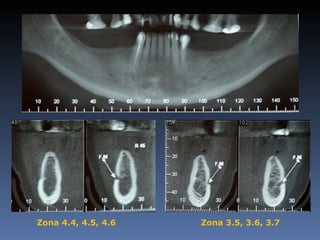

BOX 3 Kátia MariaCavicchia Idade – 43 anos Sexo – Feminino Raça – Caucasiana ASA – II Data- 29-04-2012 Diagnóstico: Desdentado parcial bilateral posterior da mandíbula. Plano de tratamento: Reabilitação bilateral posterior mandibular com instalação de 6 implantes endo- ósseos, para reabilitação protética fixa.

• 158.

Zona 4.4, 4.5,4.6 Zona 3.5, 3.6, 3.7